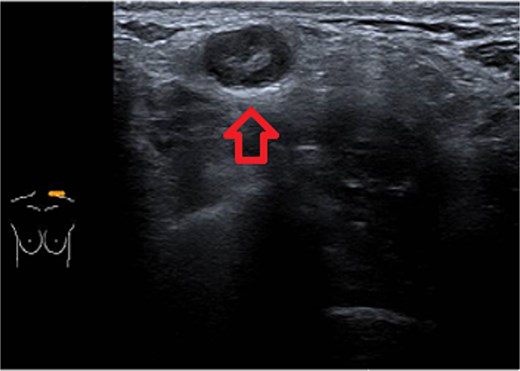

Ultrasound of left breast and axilla: Revealed rupture of the left implant with intracapsular and extracapsular leakage, along with echogenic peri-implant fluid. Enlarged axillary lymph nodes were visualized (Figs 1 and 2).

Ultrasound of the left axilla showed the typical appearance of the lymph node siliconoma.